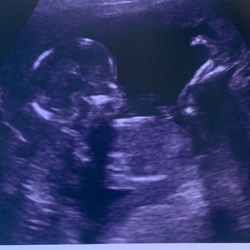

Ik zat al te denken of het nu komt van het weer, de ventilator thuis/airco op het werk, hooikoorts of gewoon van de zwangerschap. 🤷🏻♀️